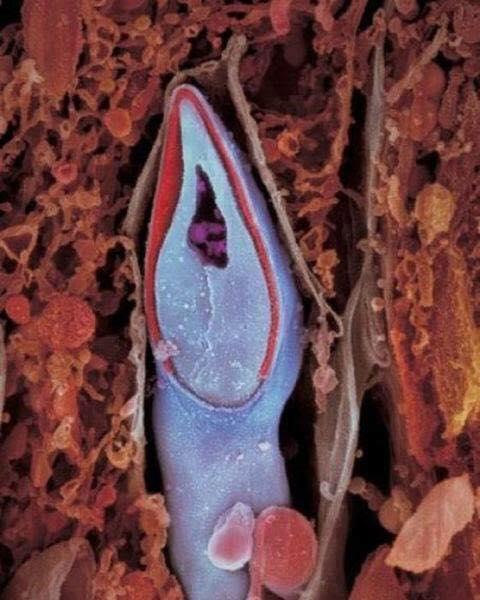

8 dias depois, embrião implantado na parede do útero